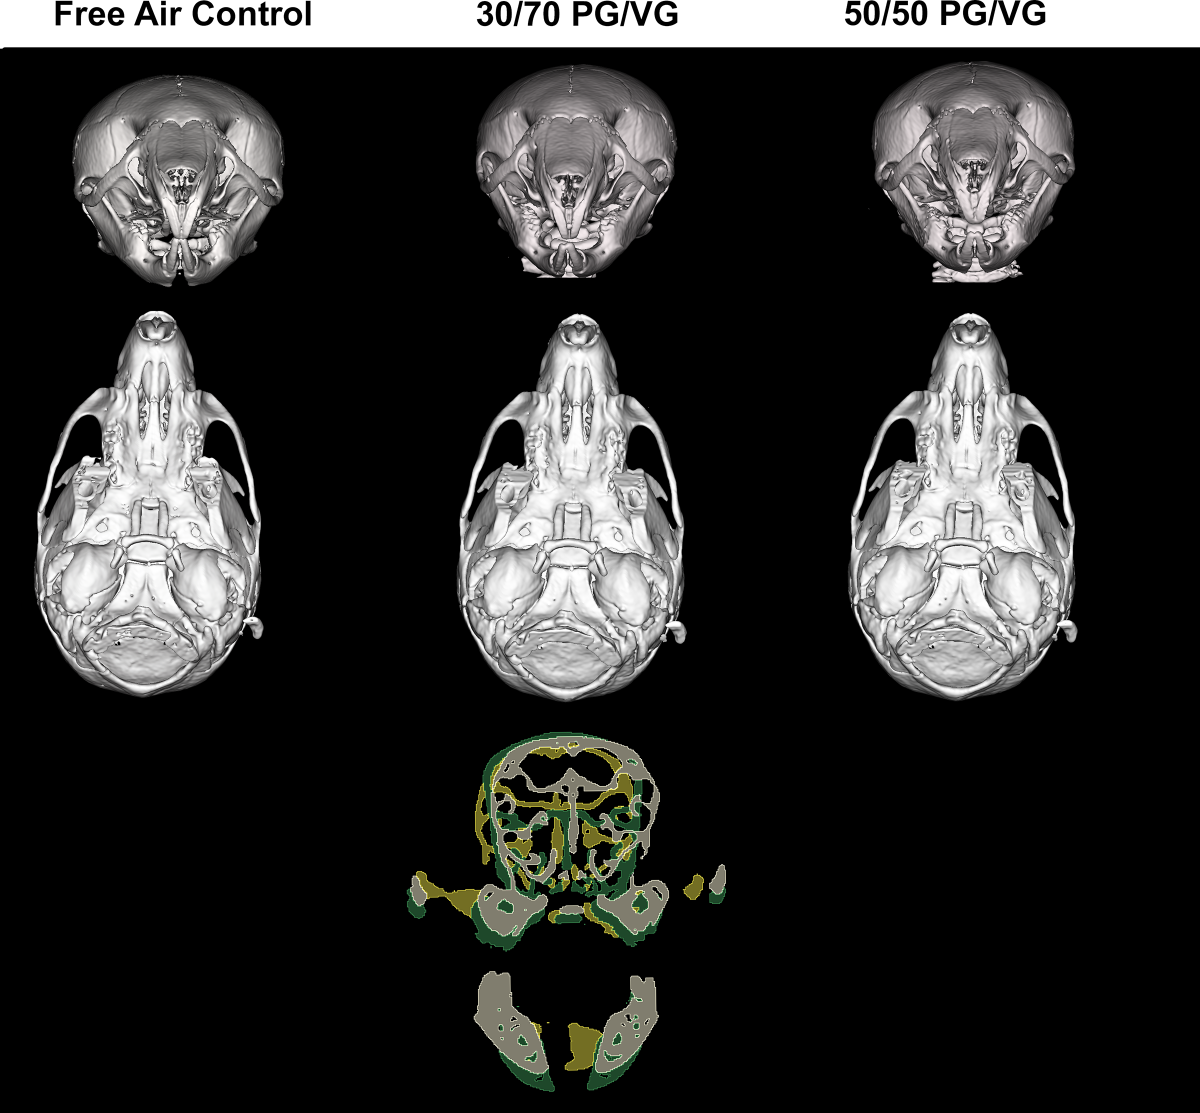

전자담배 액상 성분으로 많이 쓰이는 프로필렌 글리콜(PG)과 글리세롤(VG)의 비율을 각각 3 대 7과 5 대 5로 혼합한 에어로졸에 임신한 쥐가 노출됐을 때 새끼 쥐의 두개골 모양과 크기를 비교한 이미지. 플로스원 캡처

프로필렌 글리콜과 글리세롤 비율이 5 대 5인 에어로졸에 노출된 어미에서 태어난 쥐는 신선한 공기를 마신 대조군과 유의미한 차이를 보이지 않았다.

오히려 글리세롤 비율이 높은 에어로졸에 노출된 어미에서 태어난 쥐는 다른 그룹에 비해 두개골과 얼굴이 너비나 길이 측면에서 상당히 작았고, 코도 짧았다.